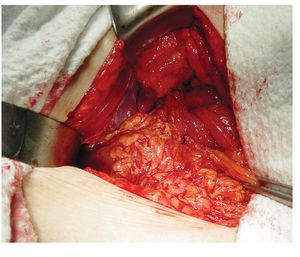

Se trata de paciente femenino de 75 años de edad, la cual acude al servicio de urgencias por presencia de vómitos en varias ocasiones de contenido gástrico, intolerancia a los alimentos, malestar generalizado y datos francos de deshidratación secundaria, con 15 días de evolución desde el inicio de su padecimiento. La paciente tiene antecedentes de diabetes mellitus, hipertensión arterial y refiere gastritis crónica en tratamiento. A su ingreso se encuentra orientada, conciente y sin datos de alarma abdominal, por lo que es internada para su estudio y estabilización con sospecha de cuadro de estenosis péptica pilórica. Se coloca sonda nasogástrica drenando aproximadamente 3 L de material gástrico espeso y restos de alimentos. Laboratorios a su ingreso con hemoglobina de 10 mg/dL, leucocitosis de 13,000 mm3, glucosa 96 mg/dL, urea 30 mg/dL, creatinina 1.8 mg/ dL. Una vez con la paciente en mejores condiciones, se decide realizar panendoscopia encontrando un cálculo biliar gigante impactado en el bulbo duodenal (Imágenes 1 y 2) realizándose múltiples maniobras de extracción con pinzas de cuerpo extraño, las cuales no fueron exitosas. Se realizó ultrasonido demostrando la presencia del cálculo impactado en duodeno, no se apreció dilatación de vías biliares (Imagen 3). Con estos hallazgos se decide someter a la paciente a cirugía, encontrando la presencia de un cálculo biliar gigante dentro del bulbo duodenal con vesícula biliar escleroatrófica, se realiza duodenotomía y extracción del cálculo con duodenorrafia en 2 planos tipo Heineken-Mikulicz sin incidentes transoperatorios (Imágenes 4, 5 y 6) y con adecuada evolución, siendo egresada al octavo día del posoperatorio.

Imagen 5. Duodenorrafia en 2 planos tipo Heineken-Mickulicz y parche de epiplón.